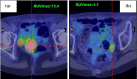

The incidence of endometrial serous carcinoma (ESC) has been increasing, and ESC is resistant to treatment. We report a patient with ESC who responded to radiotherapy for multiple recurrences. The first recurrence was detected in the vaginal wall and left internal iliac lymph node 5 months after the initial treatment. Concurrent chemoradiotherapy (CCRT) was administered. Radiation was delivered using the intensity modulated radiation therapy technique. The second recurrent tumor was detected in the right internal iliac lymph node after 4 months, and CCRT was conducted. After 4 months, the third recurrence was detected in the right common iliac node, and CCRT was performed. After 8 months, the fourth recurrence was detected in the horizontal portion of the duodenum, and radiotherapy was administered. After 9 months, the fifth recurrence was detected in the vaginal wall. Interstitial brachytherapy was conducted. Grade 2 gastrointestinal injury, nausea and radiodermatitis were observed. During the subsequent 13-month follow-up, there has been no recurrence. Although ESC is resistant to treatment, radiotherapy could be effective in some cases. Even when multiple recurrences occur, radiotherapy may be considered a treatment option if the irradiation level is permissible.